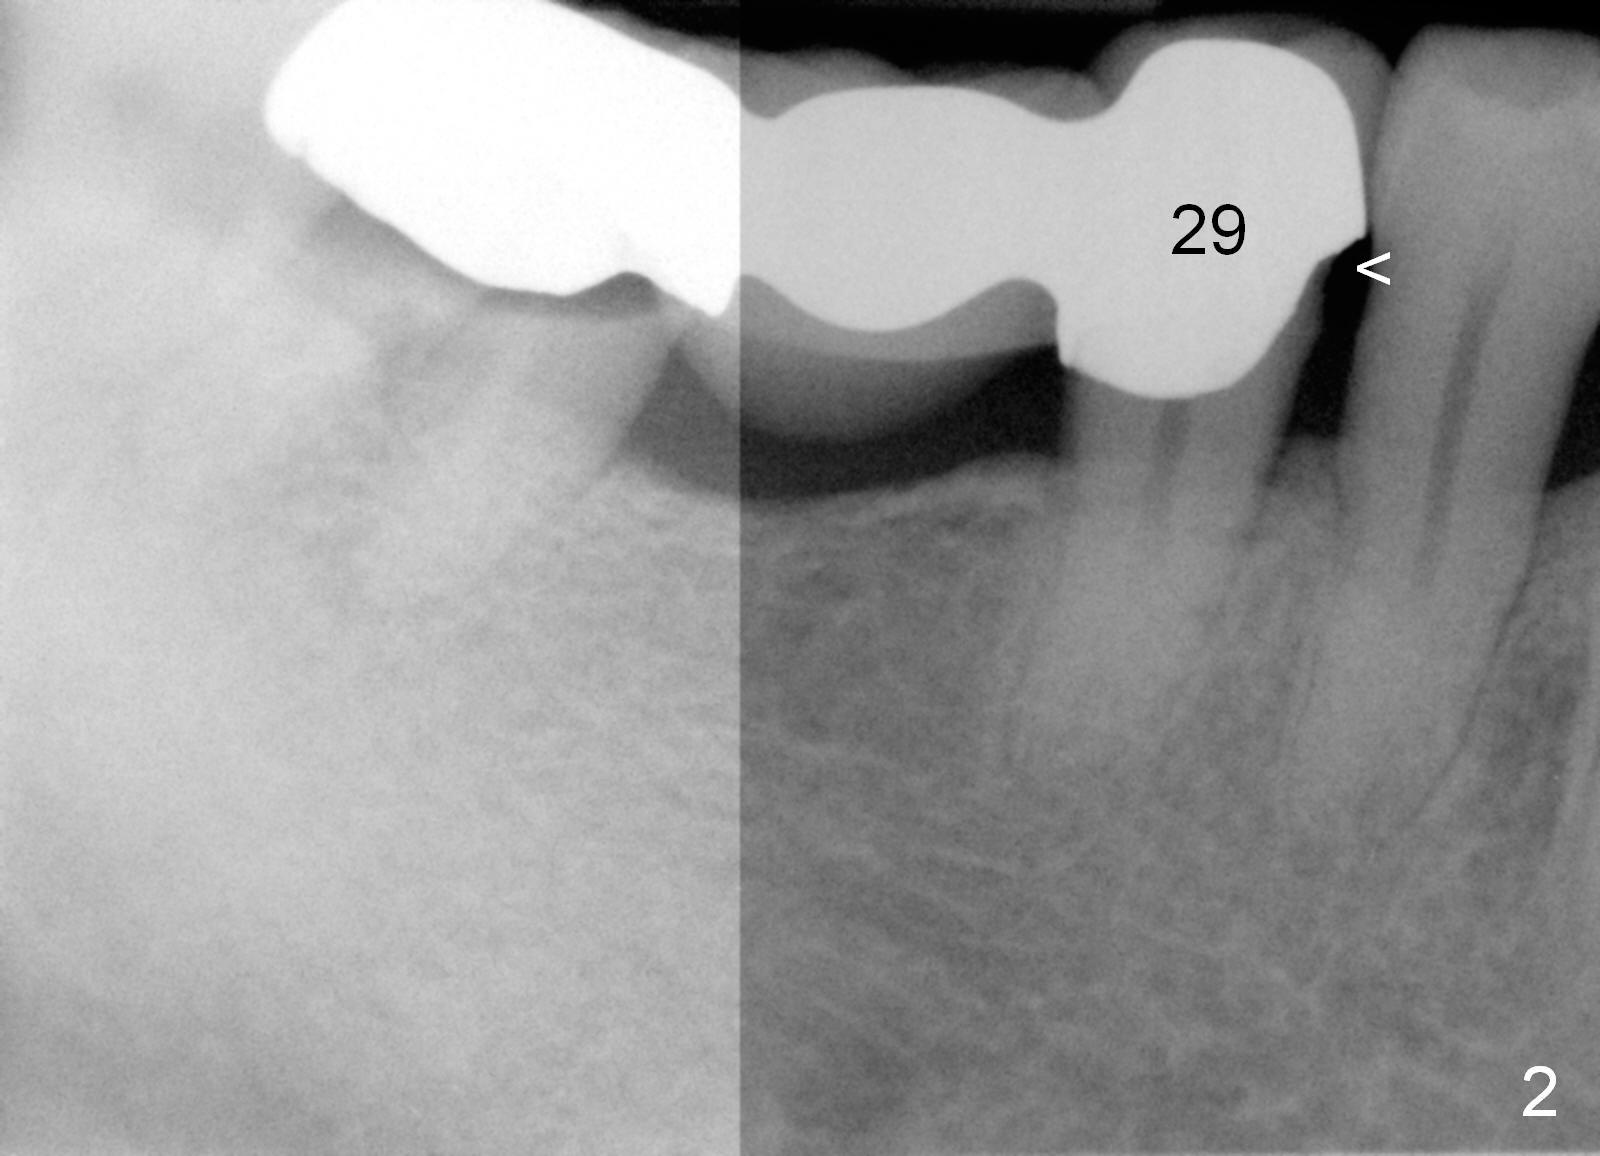

A 47-year-old man works in Africa.  While he is visiting his family at Atlanta, he has toothache in the lower right.  Examination reveals secondary caries under #31 retainer (Fig.1) and mesial open margin of #28 retainer (Fig.2).  Surgery is scheduled next day.